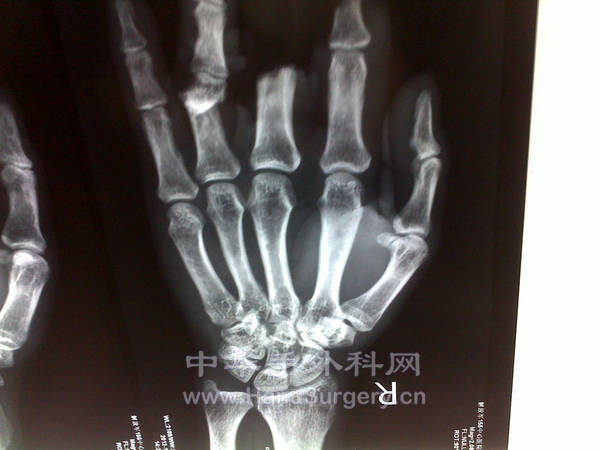

患者因机器压扎伤右手示、中、环指入院。

示、中指毁损,未找到,一期残修,二期再造。

环指近节掌侧皮肤缺损,曲肌腱外露,双侧指固有动脉缺损。

术前X片